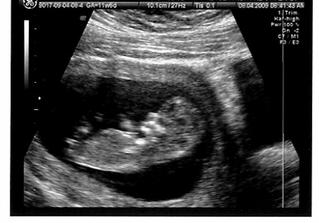

8.4.2009 NT screening, máme 2 ruce, 2 nohy, krásný nosánek, měříme po zadeček 5,17cm, s nožičkama cca + 2,5cm. Máme v bříšku malýho neposedu, pan doktor říkal, že je šíleně aktivní :o) A aktivní dítě je podle něj šťastný a spokojený dítě :o)